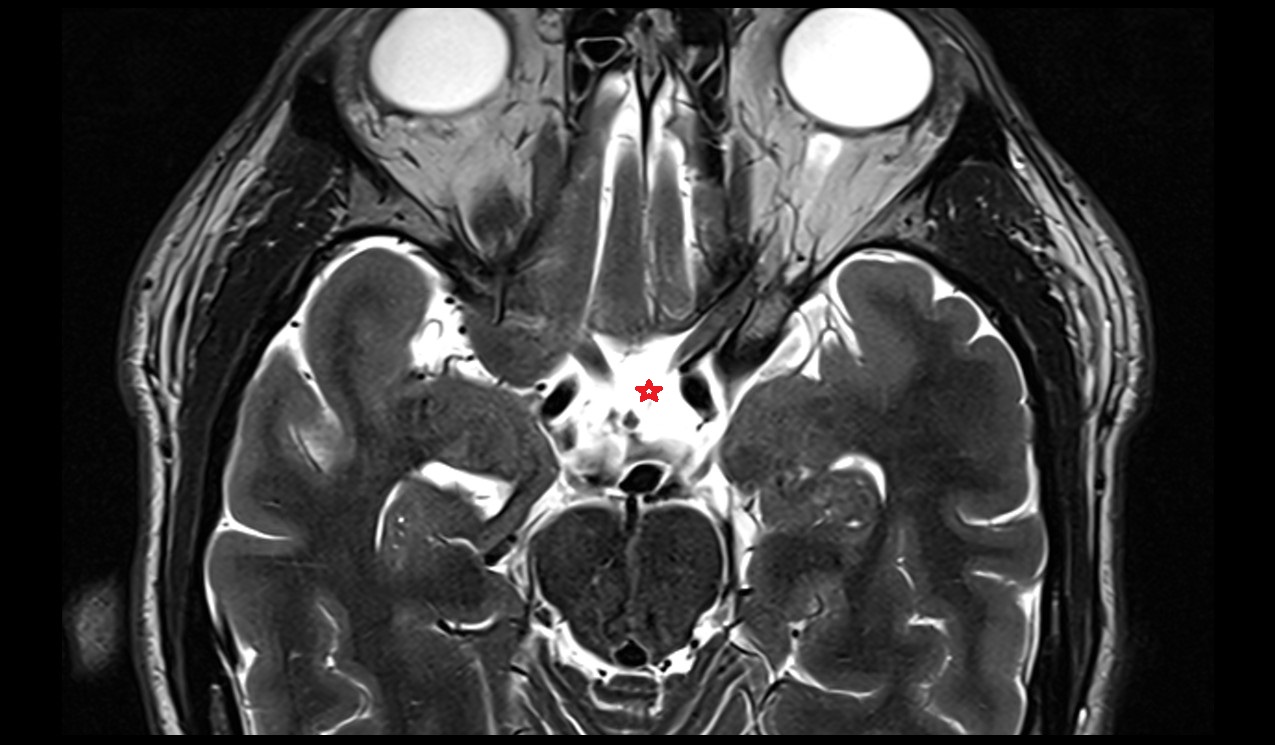

- Interpeduncular Cistern

- Interpeduncular fossa